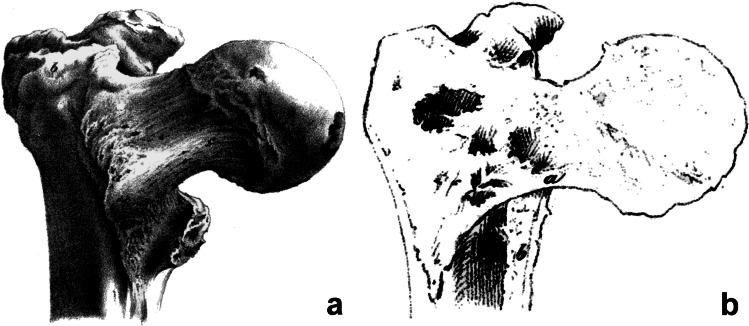

Adams was not the only one at this time to address the structure of the proximal femur. In 1838, a 20-year-old medical student Frederick Oldfield Ward (1818–1877) described in the book Human Osteology [27] the structure of the proximal femur accompanied by a drawing (Fig. 4), which has been discussed ever since [28]. Georg Hermann von Meyer (1815–1892), an outstanding German anatomist living in Zurich, published a study “Die Architectur der Spongiosa” in 1867 [29] in which he analyzed in detail the internal architecture of the proximal femur (Fig. 4). The German anatomist Friedrich Julius Wolff (1836–1902) focused, in his monograph “Das Gesetz der Transformation der Knochen” (The law of bone remodeling) of 1892 [30], on the internal architecture of the proximal femur, discussed the Ward’s and von Meyer’s concepts, and summarized all the findings in this field.

Fig. 4.

Internal architecture of the femur after Adams [9], Ward [27], and von Meyer [29]

However, none of these authors mentioned Adams. The same applies to the major textbook of anatomy of that time [31–35]. It may be explained by the fact that Adams dealt only with the thickened medial cortex of the femoral neck, while Ward and von Meyer discussed the wider structure of the proximal femur in much greater detail.

Fig. 5.

Relationship between the Adams’ arch (AA) and the calcar femorale (CF) on the right proximal femur. The posterior cortex in the region of the lesser trochanter was removed